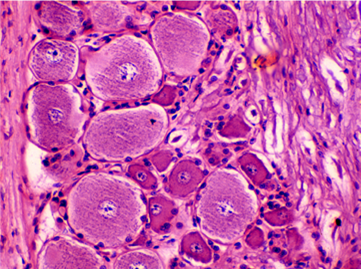

图23 有髓神经纤维束横切面光镜图 (1轴突 2髓鞘 3施万细胞核 4神经束